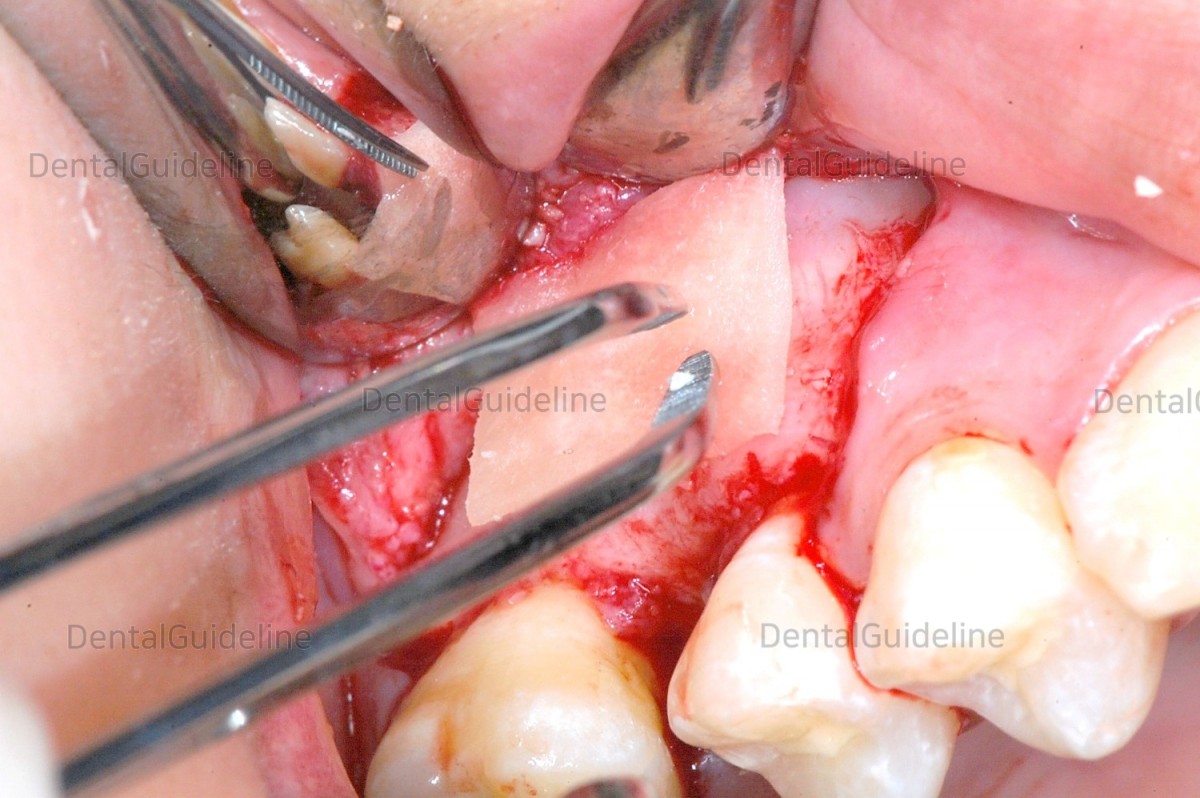

3. For the laterally approached maxillary sinus graft, the

lateral window was opened using a Pizo piezo surgical equipment

(SURGYBONE®, SIILFRADENAT Co,)

4. AIO(All-In-One) sinus curette was used.

5. The maxillary sinus membrane was sufficiently raised.